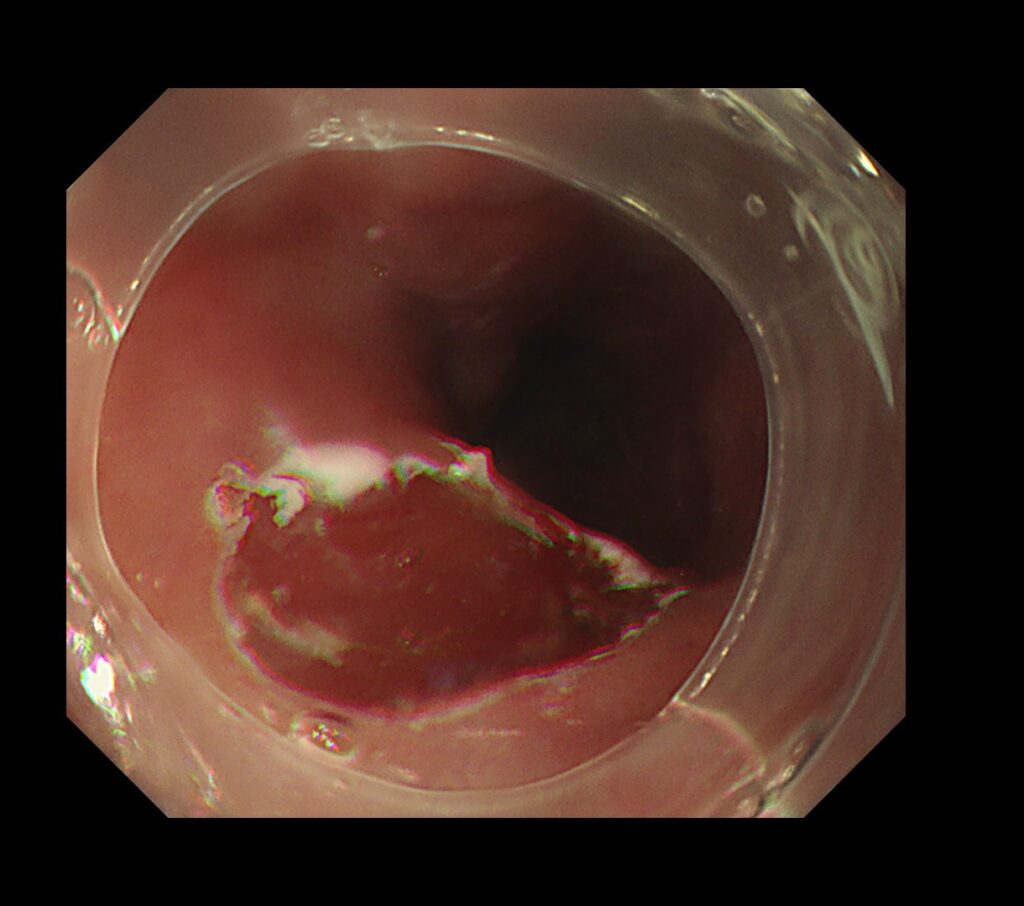

癌部に電気メスでマーキングをし、10分程度で、高周波を使用し、一括切除しました。